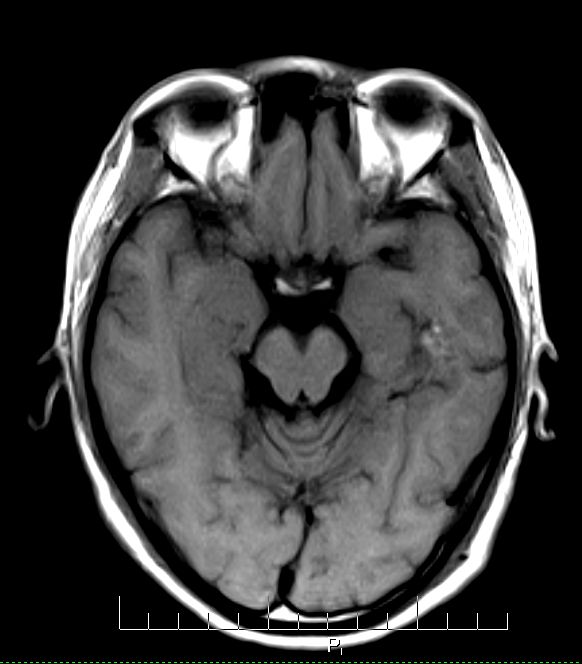

标题: MRI2379:30岁,男,癫痫10年,请各位看一下;CT示:左颞叶钙 [打印本页]

标题: MRI2379:30岁,男,癫痫10年,请各位看一下;CT示:左颞叶钙

左颞叶区见不规则点状混杂信号影

考虑血管畸形

支持2楼 左颞叶区见不规则点状混杂信号影,考虑动静脉畸形。

考虑左侧颞叶脑血管畸形(avm)。

考虑左侧颞叶脑血管畸形(avm)。----t1低等高混杂信号,t2等高信号周边较多流空血管影[冠状位明显],mra左侧大脑中动脉受压,远侧聚集.